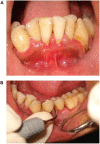

Dental plaque is considered to be a major etiological factor in the development of periodontal disease. Accordingly, the elimination of supra- and sub-gingival plaque and calculus is the cornerstone of periodontal therapy. Dental calculus is mineralized plaque; because it is porous, it can absorb various toxic products that can damage the periodontal tissues. Hence, calculus should be accurately detected and thoroughly removed for adequate periodontal therapy. Many techniques have been used to identify and remove calculus deposits present on the root surface. The purpose of this review was to compile the various methods and their advantages for the detection and removal of calculus.